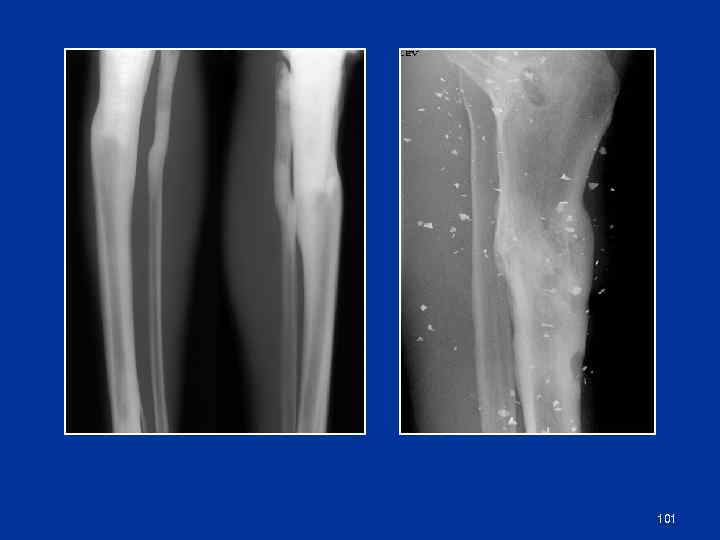

Морфологически выделяют 3 вида мозоли: эндостальная, периостальная, интермедиарная Ø Ø При полной неподвижности (металлоостеосинтез) сращение проходит 2 стадии: соединительнотканную и костную. Костная мозоль образуется между кортикальными слоями (интермедиарная костная мозоль) При значительной подвижности возникает вторичный вариант сращения в 3 стадии (соединительно-тканная, хрящевая, костная). В этом случае выражены периостальная и эндостальная костные мозоли 98

99

100

101